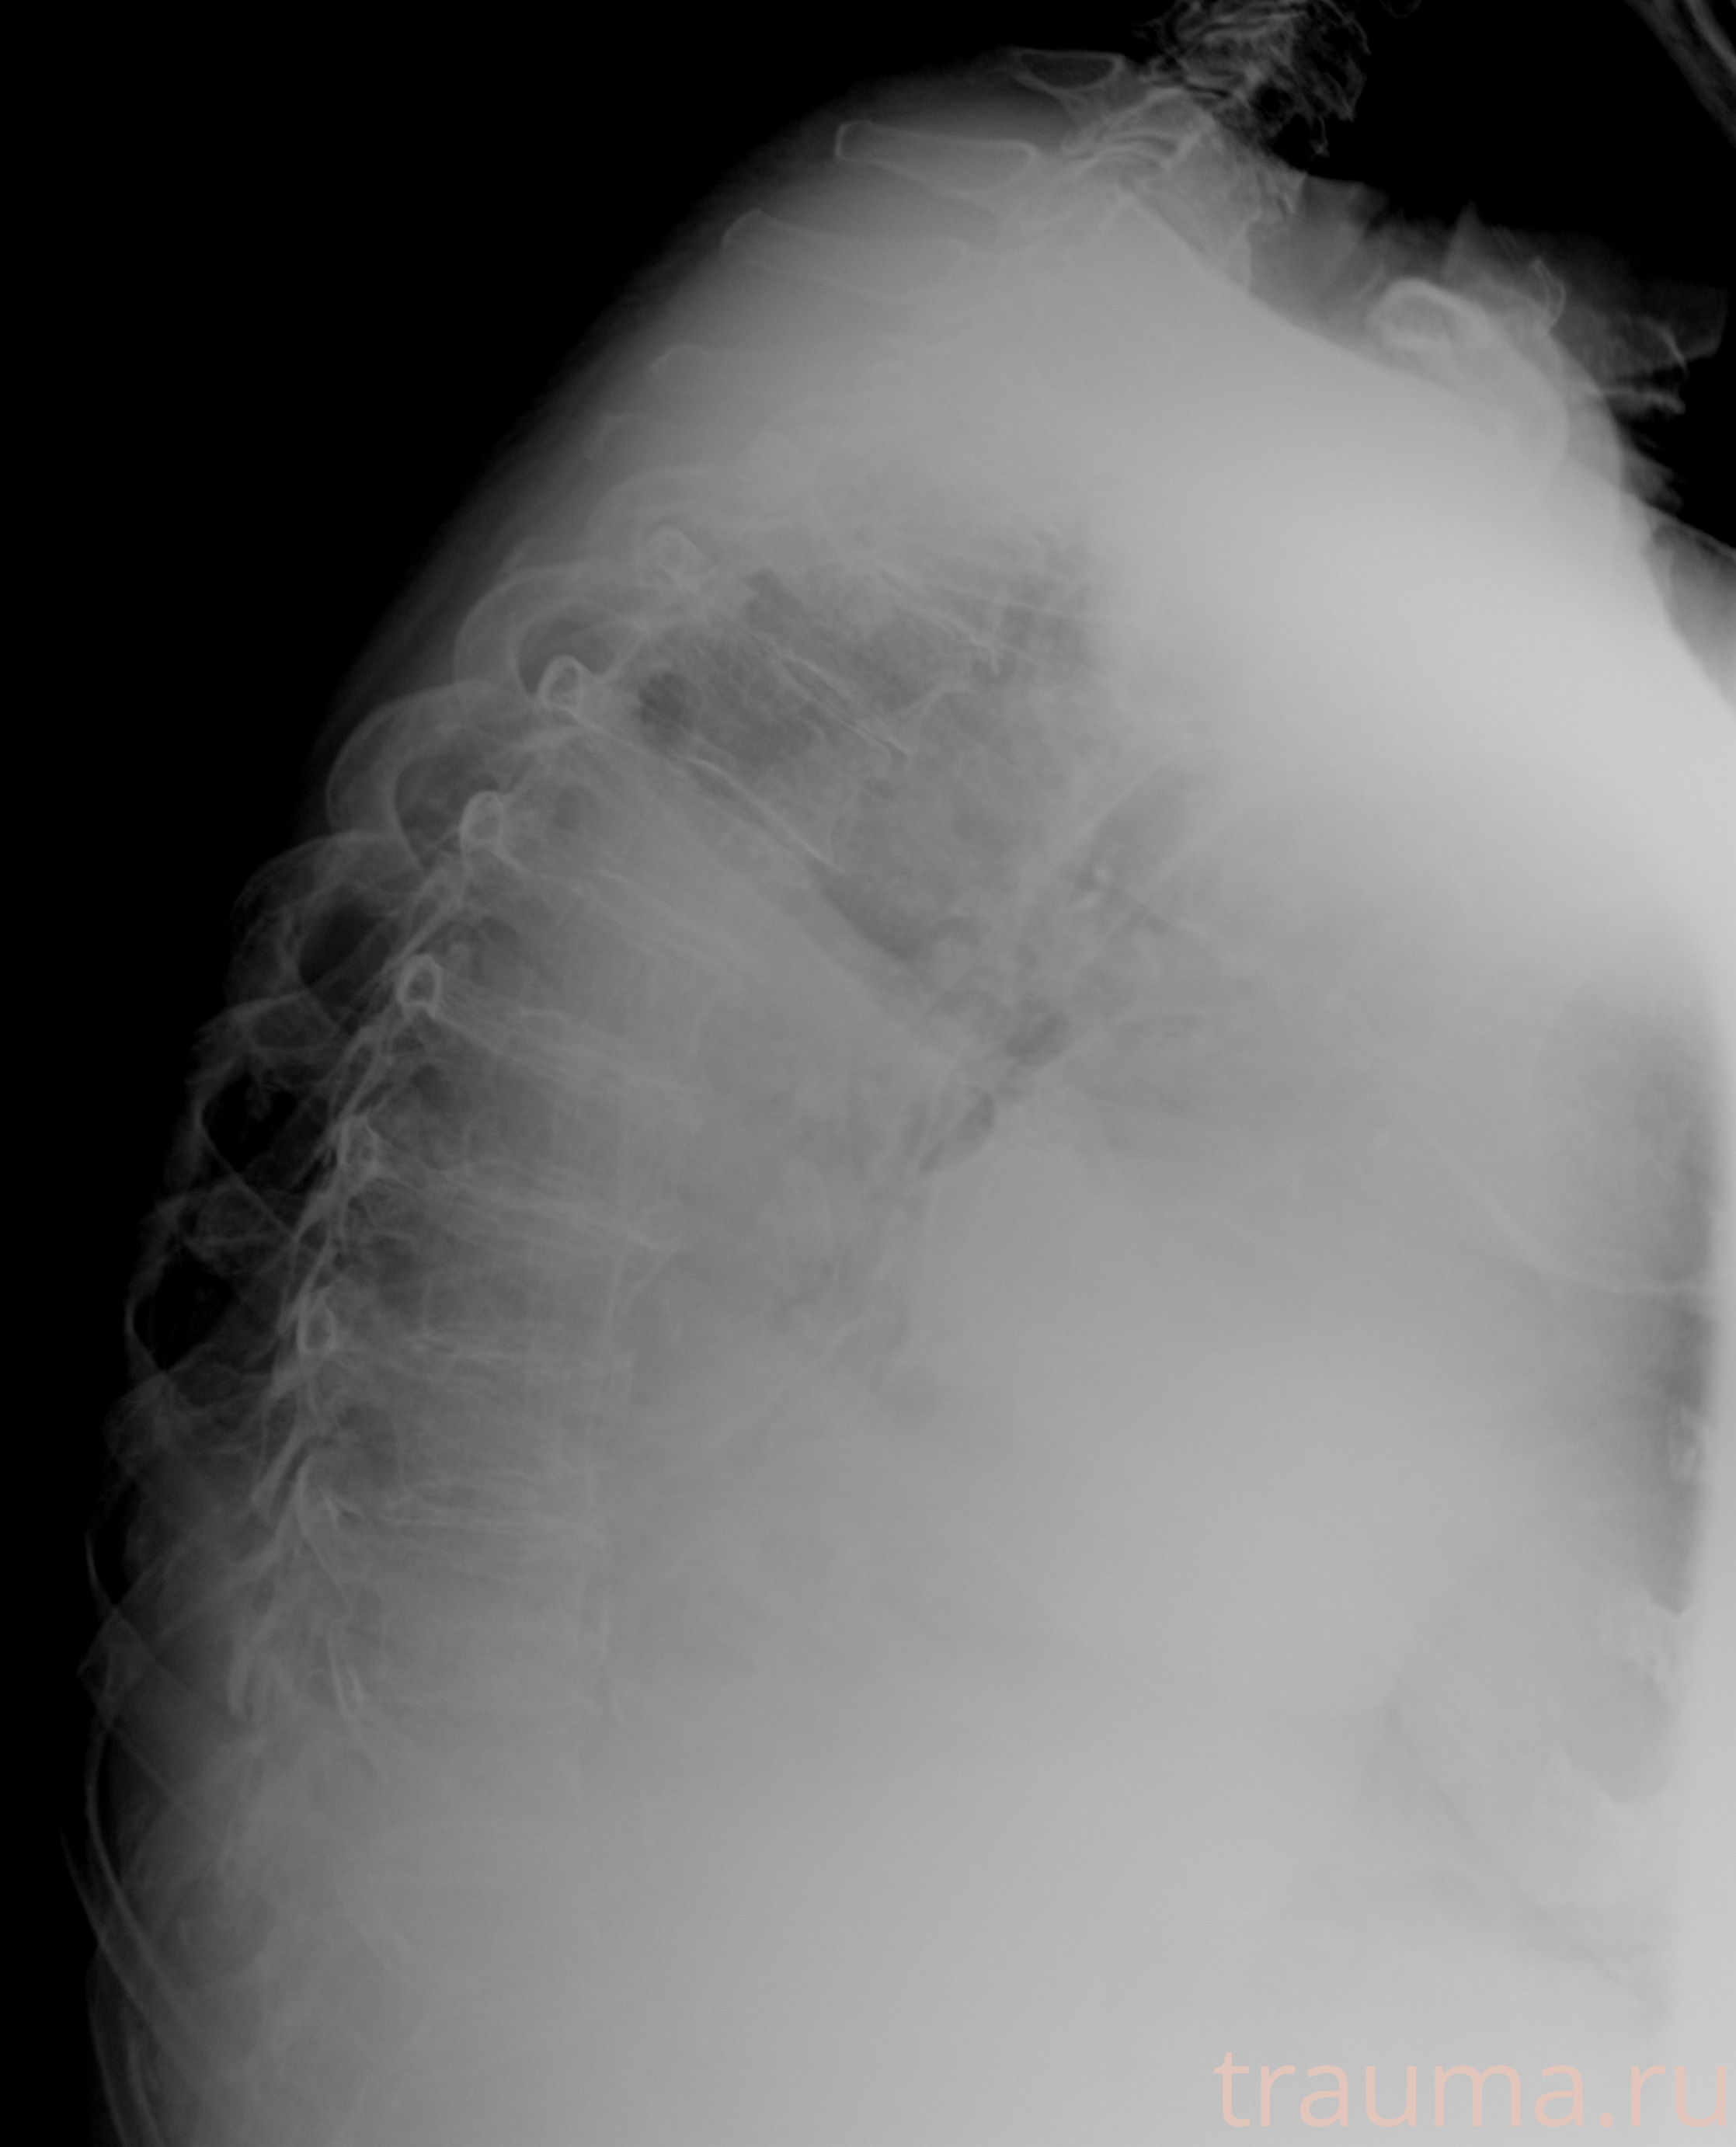

Рентгенограммы

Рентген на дому: по вашему адресу приезжает врач-рентгенолог, травматолог-ортопед с мобильным рентгеновским аппаратом, проводит диагностику травмы или заболевания, делает необходимые рентгенограммы, дает рекомендации по дальнейшему лечению. Получить качественные снимки в домашних условиях возможно благодаря уникальной методике, разработанной МосРентген Центром для института  Склифосовского

при переломе шейки бедра и пневмонии от компании МосРентген Центр - партнера Института имени Склифосовского